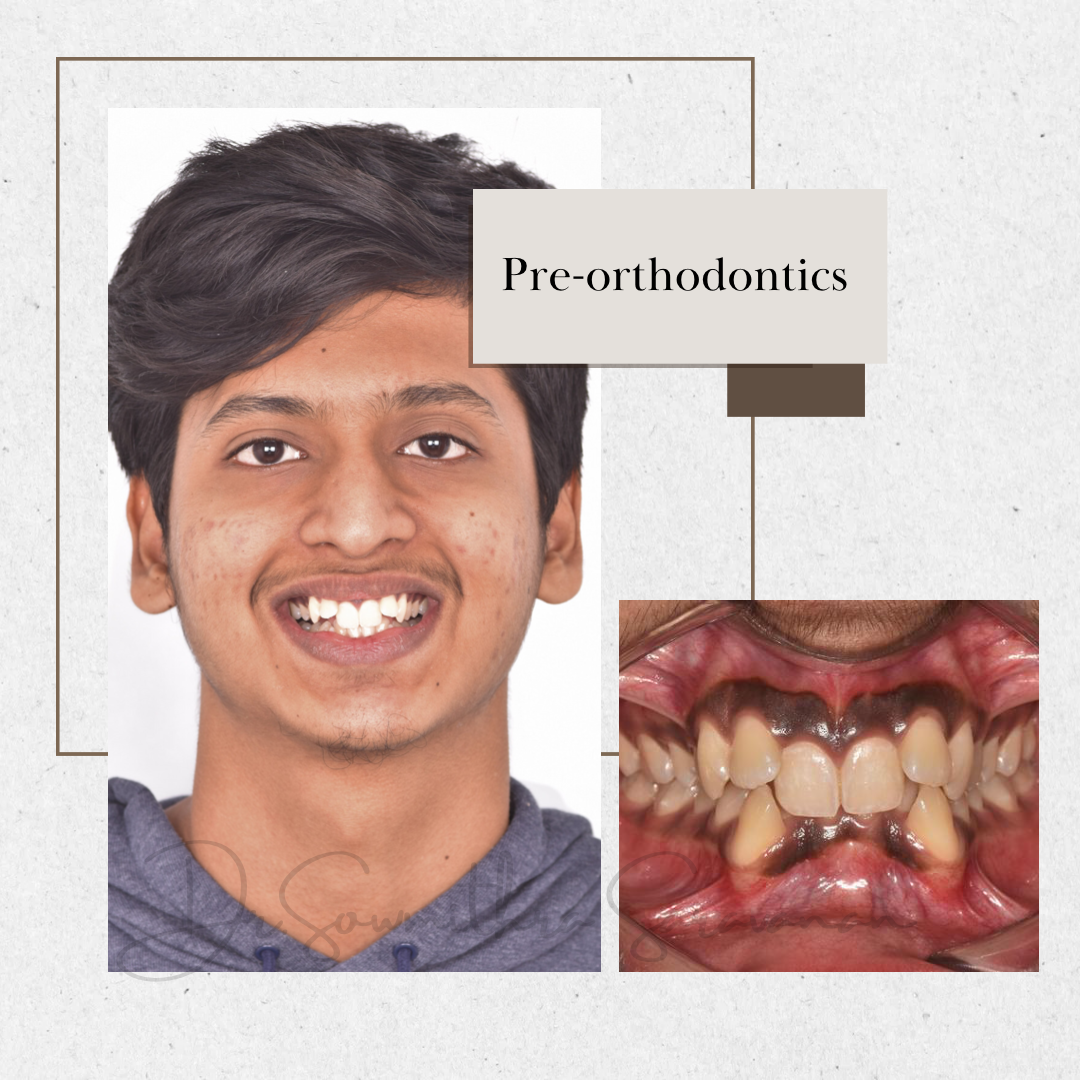

BRINGING OUT CONFIDENT SMILES- AN ORTHODONTIC SMILE REVEAL

BRINGING OUT CONFIDENT SMILES- AN ORTHODONTIC SMILE REVEAL